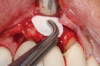

Following infiltration of the facial attached gingiva and palatal area with articaine hydrochloride 4% and epinephrine 1:100,000 (Septocaine®, Septodont [alternatively: Articadent®, Dentsply Sirona; Orabloc®, Pierrel]), an envelope releasing incision was made extending one full tooth over. To prevent trauma to the mucosal tissue, vertical incisions were not made (Figure 3). Incising the mucosa results in the release of prostaglandins and histamine, which increases postoperative discomfort. For this patient, staying in attached gingiva provided excellent control of the flap and allowed clear access to the apical lesion.

(3.) An envelope reflection was made with no vertical incisions, exposing the entire bony defect affecting the apical portion of the stable implant.

Figure 3